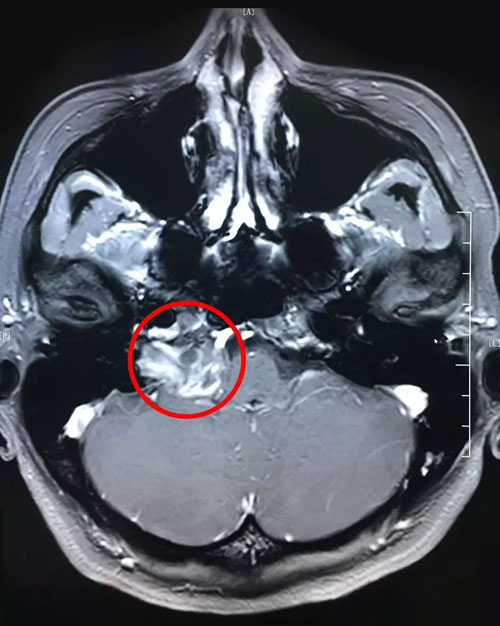

從最新的影像資料上來(lái)看,患者右側(cè)橋小腦區(qū)占位、頸深部占位,神經(jīng)鞘瘤的可能性很大。

患者術(shù)前影像:右側(cè)橋小腦區(qū)占位,頸深部占位